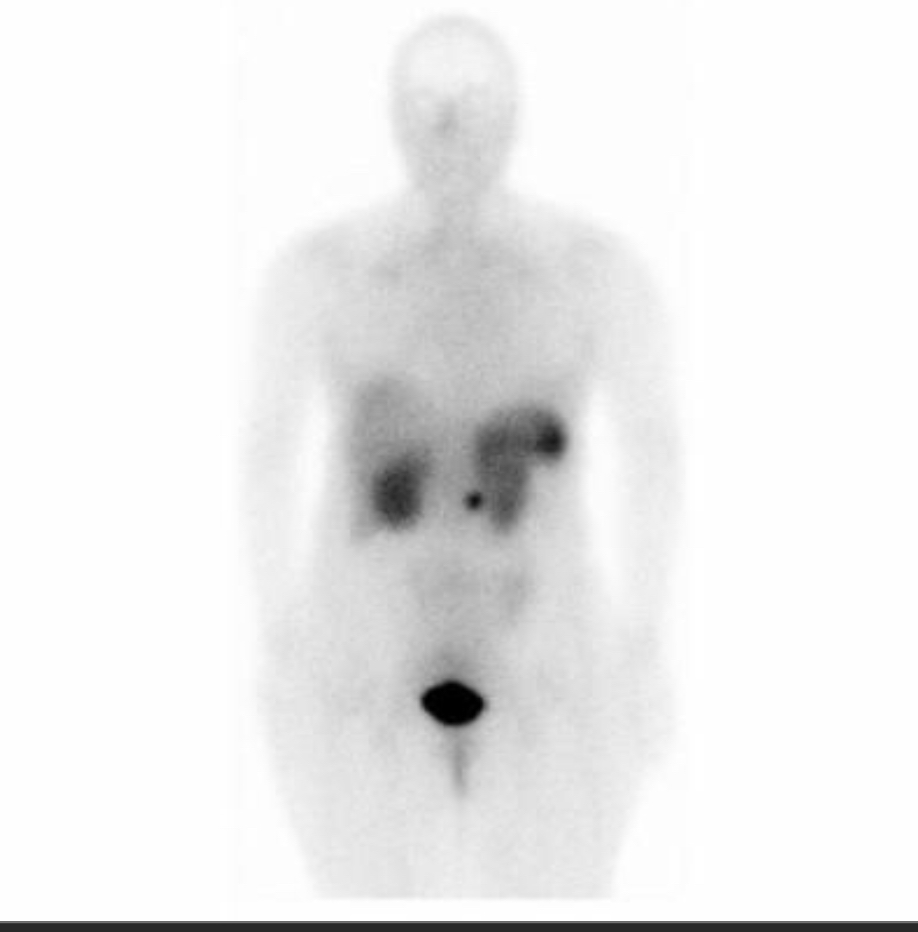

What type of scan?

Octreoscan

avid lesion in the pancreas

most likely islet cell tumor like gastrinoma or insulinoma

could also be carcinoid (more rare)